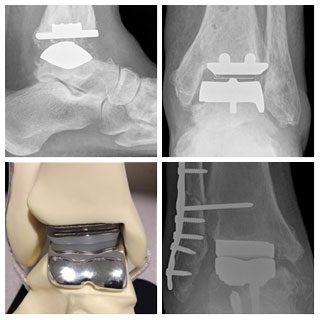

Ankle Replacement is a surgical option for a growing

number of patients with end-stage ankle arthritis. There is

very little public awareness of this procedure due to the

much smaller population of patients who have had an ankle

replacement compared to the number of patients with either

a hip or knee replacement. Many of the principles behind

ankle replacement are the same as those behind hip and

knee replacement, though the ankle has several additional

challenges.

Dr. Feinblatt has worked with all of the FDA approved ankle

replacement systems available, and was the first surgeon to implant

the STAR ankle in the State of Oregon.